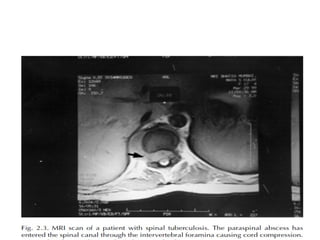

• The abscess enters the spinal canal either

through the intervertebral foramina or

through the posterior cortex of the vertebral

body